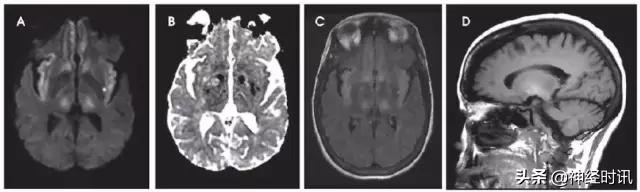

图2 一例66岁男性,癫痫发作伴意识状态改变、急性失语和右侧凝视,拟诊脑卒中并给予IV-tPA治疗。左侧病灶情况下的右侧凝视可提示癫痫发作。他的入院MRI显示左侧额顶叶皮层和皮层下白质弥散受限(A和B)和水肿(C)。他的症状和影像学(图像未提供)显示在出院前完全缓解。

图3 一例49岁女性,突然醒来出现言语不清。最初CT报告左侧MCA区域脑梗死伴左侧MCA高密度(A),MRI显示非强化(B)、T2-FLAIR高信号(C)的膨胀性病灶伴弥散增加(D-DWI,E-ADC)。活检显示为间变性少突胶质细胞瘤。